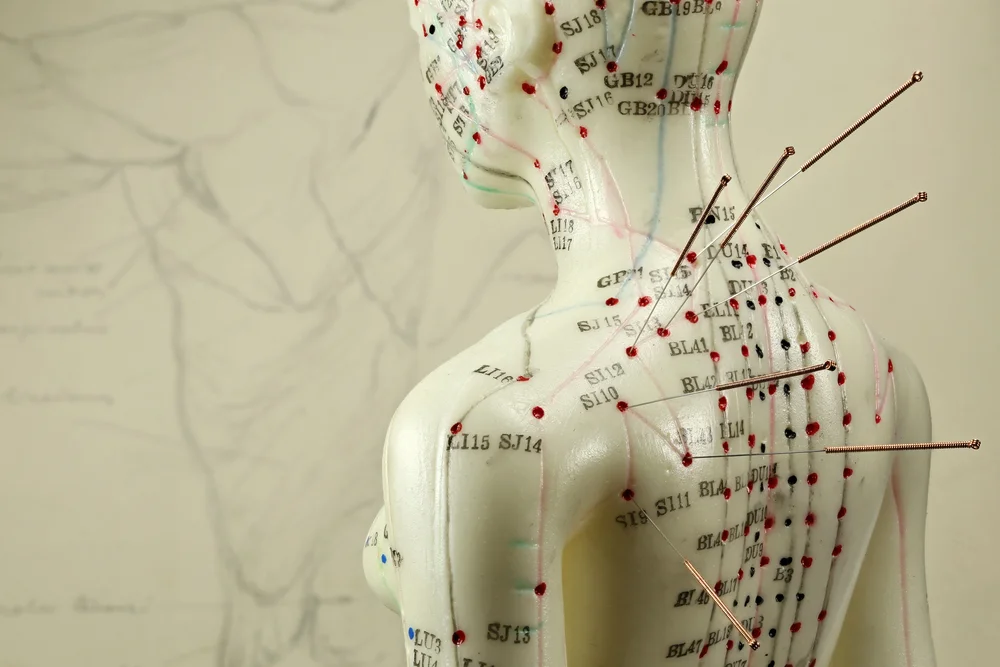

Acupuncture is a form of traditional Chinese medicine that has been used for centuries to treat these types of conditions with great success.

Our Acupuncture Pain Relief is an alternative therapy that uses needles to stimulate certain points on the body in order to heal it. It may be used in conjunction with other therapies or as a standalone treatment.

Acupuncture uses very thin needles that are inserted into the skin at specific points along energy channels in the body – called acupoints – in order to balance the flow of energy through these channels.

The needles are inserted into the skin at specific points on the body that affect muscles and joints. Some patients experience increased mobility after treatment which allows them to resume their daily activities with less discomfort. Since ancient times, acupuncture therapy has been a common practice in Eastern Asian countries.

Acupuncture is a form of Chinese Medicine that involves the insertion of needles in designated points on the body in order to stimulate the flow of energy through the meridian channels. The stimulation aids with joint and muscle function by reducing inflammation, swelling, pain, and increasing range of motion.